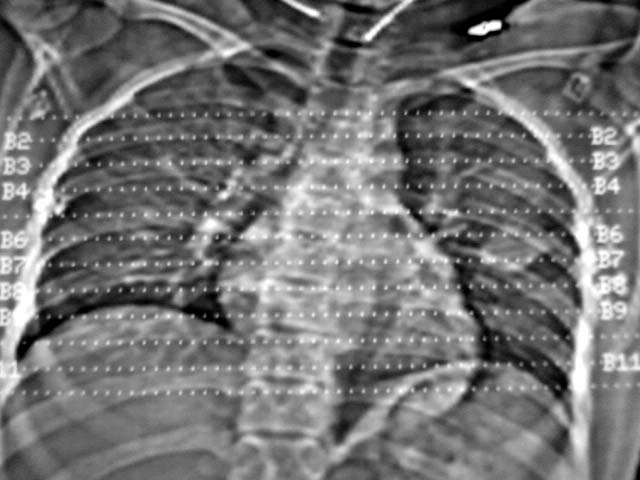

大家认为传片顺序是肺窗、纵隔窗分开传或是肺窗、纵隔交叉传,那一种更好呢?

请发表你的高见,是个人习惯或是专业方面有规定呢?

支持炎性改变。个人习惯不一,但纵隔窗与肺窗交叉看比较方便观察。